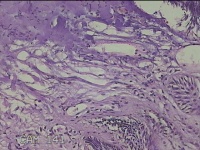

肛周外痔

1.出血性内痔 2.混合痔 3.肛乳头肥大

一般病史

间断便血3年余。

标本名称

大体所见

灰白暗红色包块0.7x0.3x0.2cm一个,表面糜烂。

像痔。

有可能是外痔。猜的。